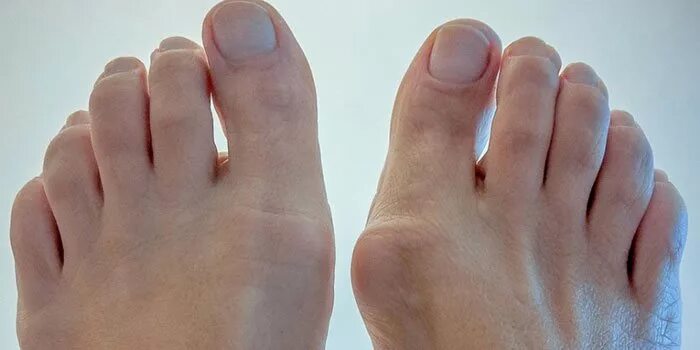

Артроз плюснефалангового сустава стопы